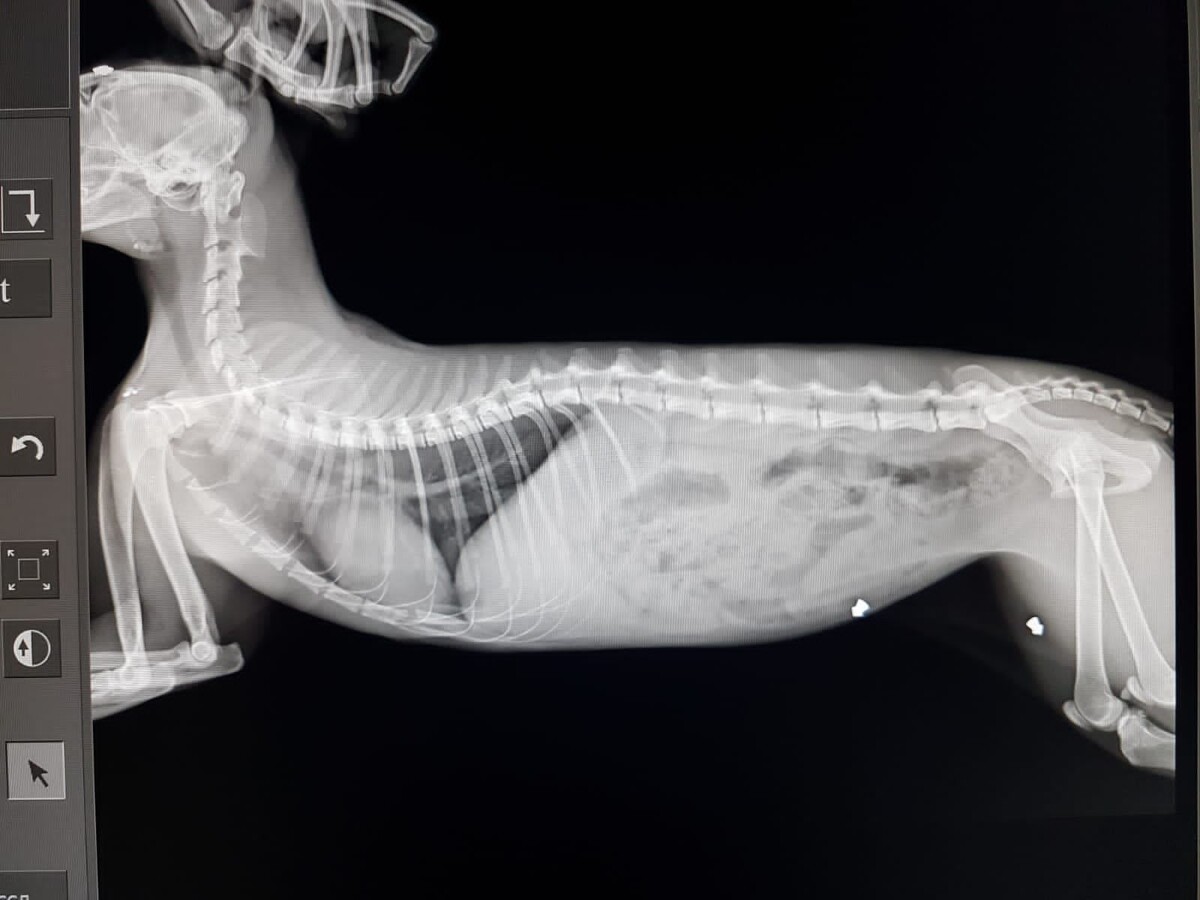

"Добрый день! Процедуры переносит хорошо. Ласковый. Аппетит хороший. Сегодня вечером будет травмалог, будем принимать решение зачищать кость или убирать секвестр (отмершую часть кости). Анализы будут готовы сегодня после 18-00."

Вчерашний день :прием и обследование оплачены. Фото прилагается.

Держим кулачки, что бы с лапкой всё было хорошо и лапку сохранили.